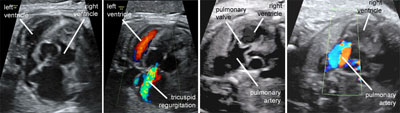

Pulmonary atresia with intact ventricular septum

Click the image to magnify it

Legend:Pulmonary atresia with intact ventricular septum: the right ventricle is small, there is significant tricuspid regurgitation, there is no flow across the pulmonary vale, and there is streaming of flow into the pulmonary artery as a consequence of retrograde perfusion through the ductus arteriosus

Reference(s):Todros T, Paladini D, Chiappa E, Russo MG, Gaglioti P, Pacileo G, Cau MA, Martinelli P. Pulmonary stenosis and atresia with intact ventricular septum during prenatal life. Ultrasound Obstet Gynecol 2003;21(3):228–33. PubMed PMID: 12666215.

Ebstein malformation of the tricuspid valve

Legend:Ebstein malformation of the tricuspid valve: the leaflets of the tricuspid valve are displaced apically compared to the atrioventricular junction and there is massive tricuspid regurgitation